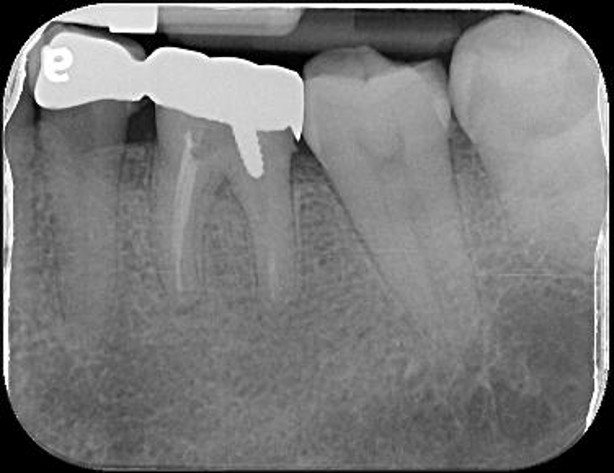

治療前,左下第二大臼齒根管鈣化

先拔除左下智齒

顯微根管治療